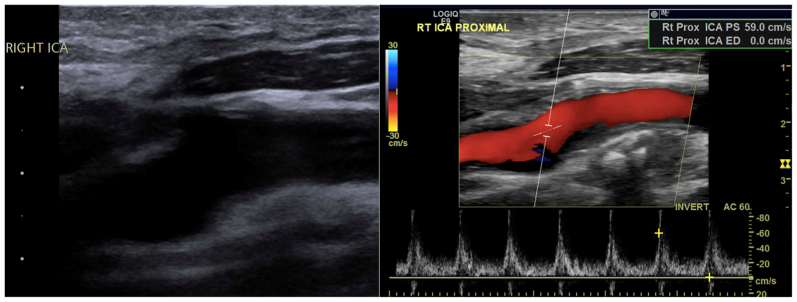

Fig 6.

Surveillance duplex ultrasound showing repaired right (RT) internal carotid artery (ICA) segment. Rt Prox ICA PS, right proximal internal carotid artery peak systolic velocity; Rt Prox ICA ED, right proximal internal carotid artery end-diastolic velocity.

Following surgery, the patient had an uneventful hospital course. The patient was discharged to home on postoperative day 1 with instructions to take daily aspirin and high-intensity statin therapy. The patient has since remained neurologically intact, with no stenosis in the right ICA and stable minimal stenosis of the contralateral carotid artery at his most recent follow-up, ∼20 months after the initial intervention (Fig 6). After extensive discussion regarding his options for prophylactic contralateral styloidectomy vs annual observation, the patient preferred to proceed with annual duplex ultrasound surveillance to monitor for worsening left carotid artery stenosis.